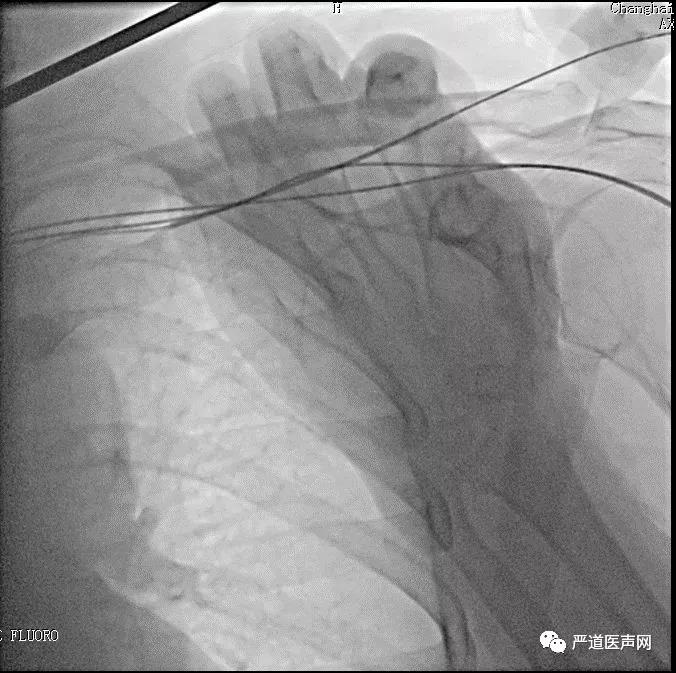

电极植入路径选择

•在左锁骨外1/3下方2cm处,切开皮肤,长约5cm,分离出头静脉作为备用。

•在造影透视下连续3次成功穿刺腋静脉。

如何快速有效寻找CS?

•我们的经验:LAO 45°投照体位

先植入右室除颤电极、再行植入左室电极

•AP位

•造影情况:LAO发现走形左室侧的靶静脉与主干分支处有迂回夹角,且靶静脉中似乎也有夹角?

•选择SION软导丝0.014X180cm,头端塑形回头弯,无法进入靶血管